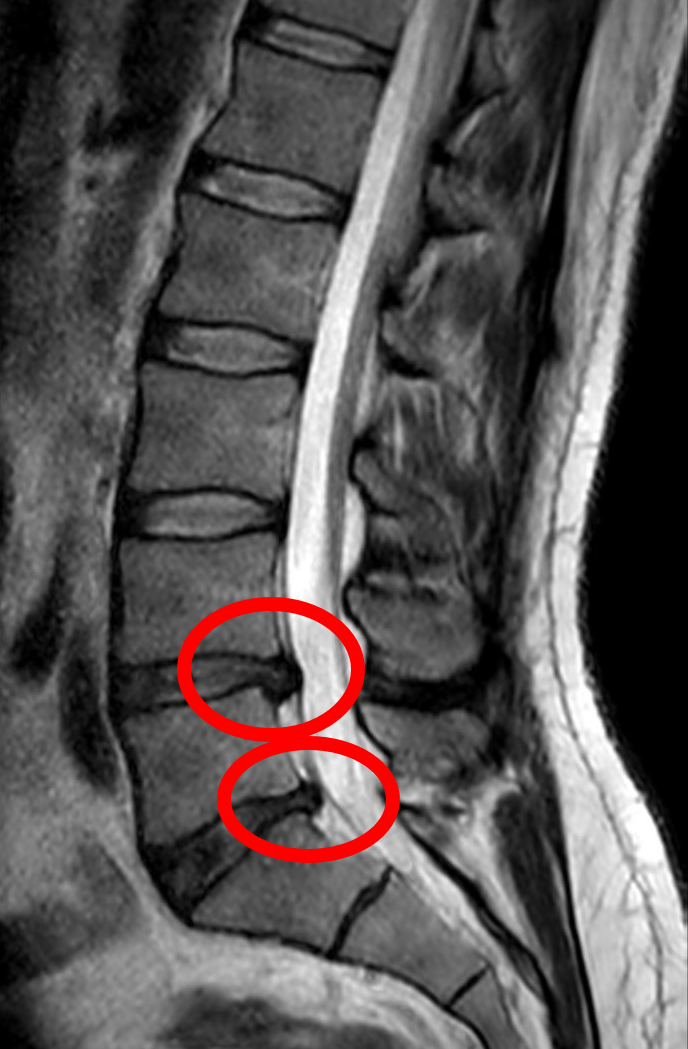

RMN lombar – hernie de disc L4-L5

Exemplu imagistic: hernie de disc lombară la nivel L4–L5.